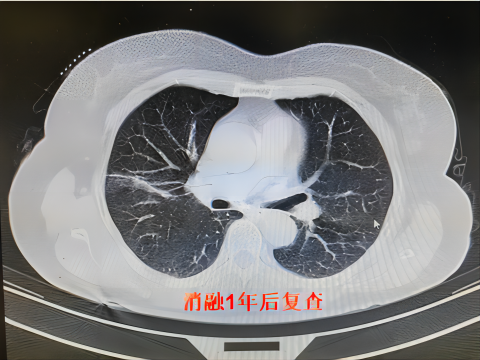

肿瘤在进行冷冻消融后,冷冻区域的“病灶”可能会显示扩大,这是正常的病理变化,只要术后按期随访观察,一般情况下,半年至一年内会吸收完全。